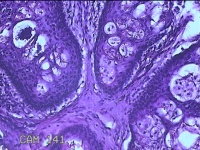

左前臂皮下结节

性别

女

年龄

42岁

临床诊断

皮下结节

一般病史

发现左前臂皮下结节2个月余。

标本名称

大体所见

灰白粉红色带皮肤结节1x0.4x0.3cm一个,表面糜烂,切开结节呈实性,切面灰白粉红色,质软。

图1